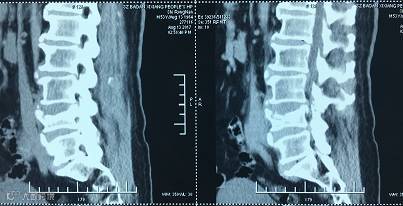

【术前CT】